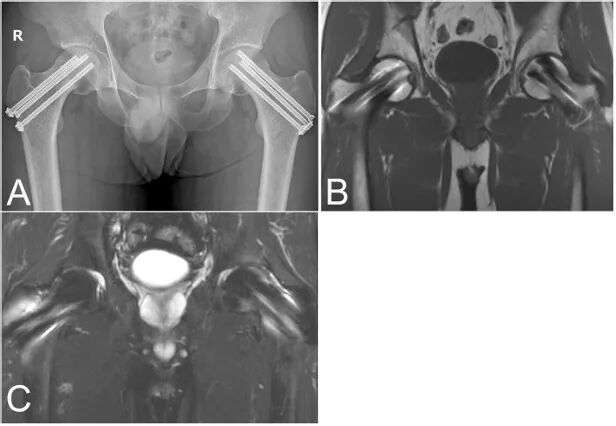

一名33岁男性因双侧腹股沟不适就诊,该症状于两周前开始。X光片显示双侧股骨颈骨折,此外,磁共振成像(MRI)发现右侧髋臼下软骨区存在骨折线。尽管患者没有明显的骨质疏松相关危险因素,但通过双能X线吸收法测得的骨密度显示严重骨质疏松(腰椎:T值−3.4标准差[SD];股骨颈:T值−2.8 SD)。血清25-羟维生素D水平不足(19 ng/mL),部分原因被认为是因为社交退缩导致3年来缺乏阳光照射。考虑到其年轻年龄,尽管骨折发生已超过两周,仍进行了双侧骨折内固定术。术后8个月的X光片和MRI确认骨折愈合良好,股骨头未发生骨坏死。